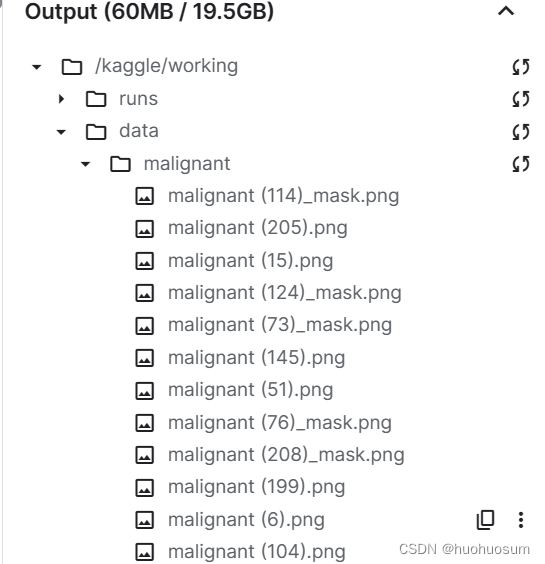

(2)读取、缩放图像并保存到工作目录

for i in range(len(class_names)):

src_list = os.listdir(os.path.join(source_dir,class_names[i]))

for j in range(len(src_list)):

img_tmp = PIL.Image.open(os.path.join(source_dir,class_names[i],src_list[j]))

img_tmp = img_tmp.resize((256,256))

img_gray = img_tmp.convert("L")

img_gray.save(os.path.join(target_dir,class_names[i],src_list[j]))

图像拷贝效果如下图所示:

(4)文件名索引中去掉掩模文件

新的数据集中有掩模文件,如果把掩模文件也作为训练数据,会降低模型性能,因此,有必要在生成文件名列表时,排除掩模文件。通过观察掩模文件命名规则可知,所有原始图像文件都是以).png结尾,可以借助os.endswith()取出所有后缀名为_mask.png的文件。代码如下:

class_names = sorted(x for x in os.listdir(data_dir) if os.path.isdir(os.path.join(data_dir, x)))

# 获取标签数量

num_class = len(class_names)

# 文件名列表

image_files = [

[os.path.join(data_dir, class_names[i], x) for x in os.listdir(os.path.join(data_dir, class_names[i]))

if x.endswith(").png")]

for i in range(num_class)

]